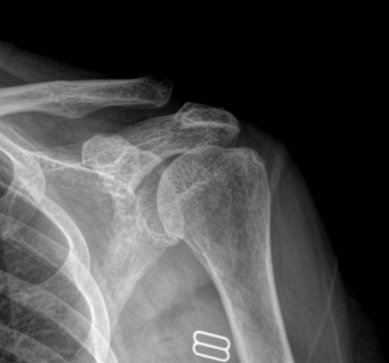

¹æ»ç¼± °Ë»ç : ¾î±ú ÀÜ¸é »çÁø¿¡¼­ ´ë°áÀýÀÇ ¹Ì¼¼ÇÑ °ñ±Ø°ú °æÈ­µÈ ¼Ò°ßÀ» º¸ÀÌ°í °ßºÀ ÇÏ´ÜÀÇ  °æÈ­ ¼Ò°ß ¹×

¿À±¸µ¹±â °ßºÀÀÎ´ë ºÎÂøºÎ °ñ±ØÀ» º¸¿© ¸¸¼ºÀûÀÎ Ãæµ¹ÀÌ ÃßÁ¤µÊ.

¿ÜÀü½Ã Àü¸é »çÁø¿¡¼­ ´ë°áÀýÀÌ °ßºÀÇÏ´Ü¿¡ Á¢ÃËÇÏ´Â ¸ð½ÀÀÌ °üÂûµÊ.

Ãæµ¹ÀÌ ÁøÇàµÇ¸é ´Ü¼ø¹æ»ç¼± ÃÔ¿µ¿¡¼­µµ Ãæµ¹ÀÇ ÈçÀûÀ» ¹ß°ßÇÒ ¼ö ÀÖ´Ù.

´Ü¼ø¹æ»ç¼± ÃÔ¿µ¿¡¼­ ´ë°áÀýÀ̳ª °ßºÀÀÇ °æÈ­¼º º¯È­(sclerotic change)  ¶Ç´Â °ñ±Ø, ´ë°áÀûÀÇ °ñ

°á¼ÕÀÌ °üÂûµÇ¸é Ãæµ¹ÀÌ ¸¸¼ºÀûÀ¸·Î ÁøÇàµÇ¾úÀ½À» ½Ã»çÇØÁØ´Ù. °ßºÀ¼â°ñ°üÀý ÇÏ´ÜÀÇ °ñ±ØÀ̳ª

caudal tilt ÃØ¿µ¿¡¼­ º¸ÀÌ´Â °ßºÀÀÇ °ñ±ØÀ» °üÂûÇϸé Ãæµ¹ ¹ß»ý °¡´É¼ºÀ» ÃßÁ¤ÇÒ ¼ö ÀÖ°í

¿À±¸µ¹±â°ßºÀÀÎ´ë °ßºÀ ºÎÂøºÎ¿¡¼­ º¸ÀÌ´Â °ñ±ØÀº ȸÀü±Ù°³ ÆÄ¿­À» °­·ÂÈ÷ ½Ã»çÇÏ´Â ¼Ò°ßÀ̰í